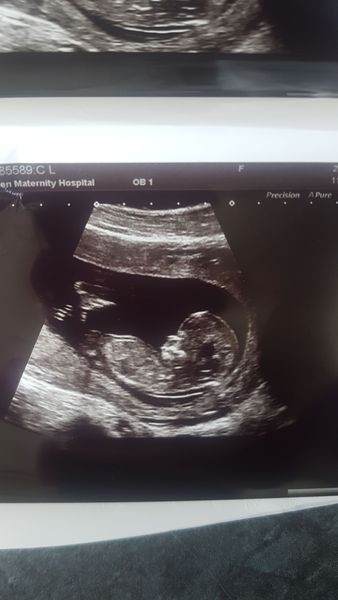

Baby160P · 23/07/2018 13:56

Lovely scan pic xx

Lovely scan pictures. Getting excited about mine now, one week today! My nausea disappeared pretty much overnight at about 11 weeks, I’m glad as we are on holiday at the moment and I’m actually able to enjoy it!

Speaking of scans - the pics today are gorgeous! I cannot wait until mine! Such a special moment.

Had my 1st scan today, everything looked good. But I may have to move to a new thread.. they've changed my due date to 30th Jan instead of 1st Feb!!

Lovely scan pictures @Celebelly and @Yakadee. Both really clear 🙂

Just seen you scan picture @loumsc. Another lovely pic! You must be so pleased 🙂

I had my harmony test scan today, there is a very wriggly baby in there. It looked like it was doing yoga!!